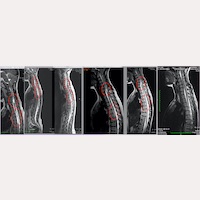

Figure.1- A patient’s magnetic resonances and their evolution following the Filum System® treatment, from the first preoperative MRI until the 7-year postoperative check-up, which shows that the medullary cysts disappeared.

“Actually”, says Dr. M. Fiallos, one of the neurosurgery team’s specialists: “not only is the progression of the syringomyelia stopped, preventing the cysts from capturing medullary tissue and its necrosis from expanding – as our patients’ postoperative MRIs show in the short term – but there are also cases in which MR images show how the cavities collapse and gradually disappear in the medium and long term, not appearing new ones (Fig.1). Sometimes, no traces of the disease are left in the neuroimaging and in parallel we can observe the patient’s clinical improvement.”